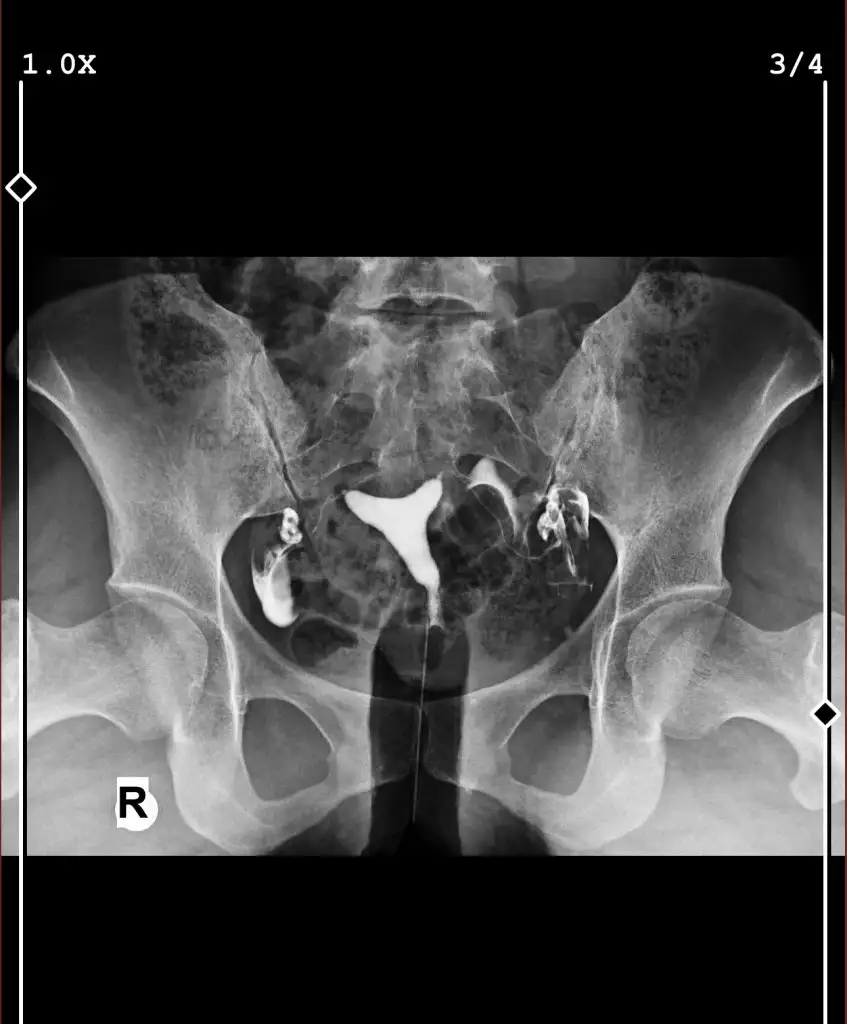

Eklentiler

• IMG_3111.webp

IMG_3111.webp

26,7 KB · Görüntüleme: 225

Bence Tüplerin açık dağılmış sıvı. rapor olarak verdilee mi ne yazıyor raporsa